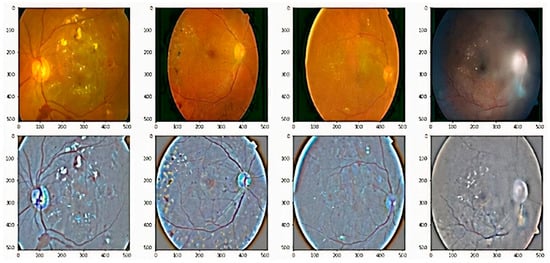

We employed various data augmentation operations on each grade differently because of the highly imbalanced nature of the dataset. The visual exemplification of some augmentation techniques performed on preprocessed images is given. This augmentation operation includes cropping, flipping, translating, shearing, rotating, zooming, Gaussian scale-space theory (GST) augmentation [], and Krizhevsky augmentation []. To produce visually appealing images, the clipping limit of CLAHE was set to 2 along the tile grid and 8, as shown in Figure 4.

Figure 4. The preprocessed retinal images after applying contrast limited adaptive histogram equalization to adjust contrast in images. (a,c) Original retinal fundus images, (b,d) preprocessed images.

For improvement of image quality and enhancement of image structure, we imployed weighted gaussian blur to the retinal fundus images. Figure 5 shows the effects of gaussian blur on the retinal fundus images. The representation of images before and after applying this method of image processing is shown in the Figure 5.

Figure 5. Some examples of adding weighted Gaussian blur to the retinal images, which is employed to reduce noise and increase image structure. First row are original fundus images, and second images are output of the preprocessed images.